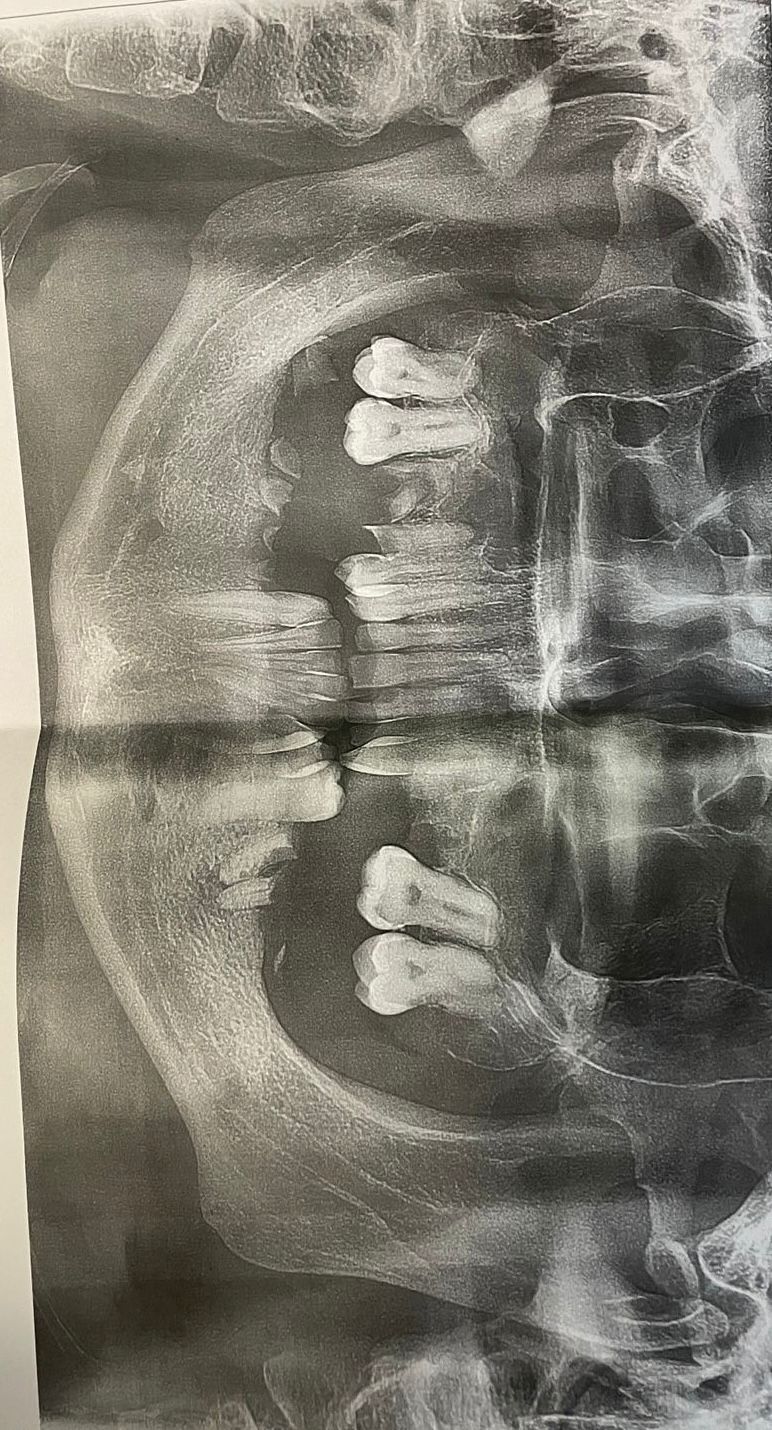

Собственно снимок, так выглядела моя челюсть, на начало лечения.

После, я опять поднялся к ортодонту на третий этаж, со снимком, чтобы он сказал план моего лечения.